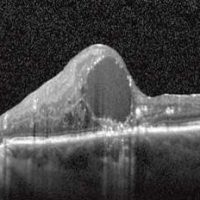

Vitreomacular Traction Syndrome

The vitreous humor is a transparent, gel-like material that fills the space within the eye between the lens and the retina. The vitreous is encapsulated in a thin shell called the vitreous cortex, and the cortex in young, healthy eyes is usually sealed to the retina.

CAUSES

Age-related degeneration of the gel-like vitreous humor leads to the formation of pockets of fluid within the vitreous, causing contraction and loss of volume. The separation of the vitreous gel from the retina occurs as a result of the gel becoming liquid (liquefaction) and the continuous anterior-posterior (front-back) and tractional forces stretching on the macula over time.